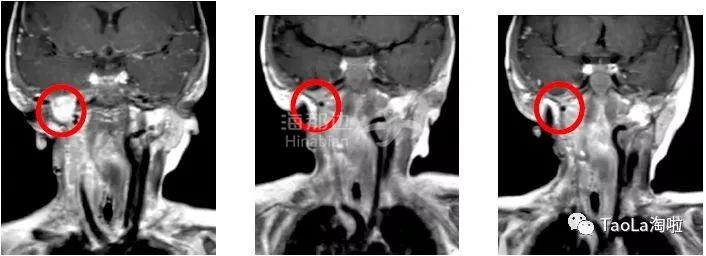

长了儿童纤维肉瘤16个月大的的婴儿接受抗癌药Vitrakvi成人剂量的液体制剂治疗3周期后,MRI磁共振显示肿瘤体积减少90%!